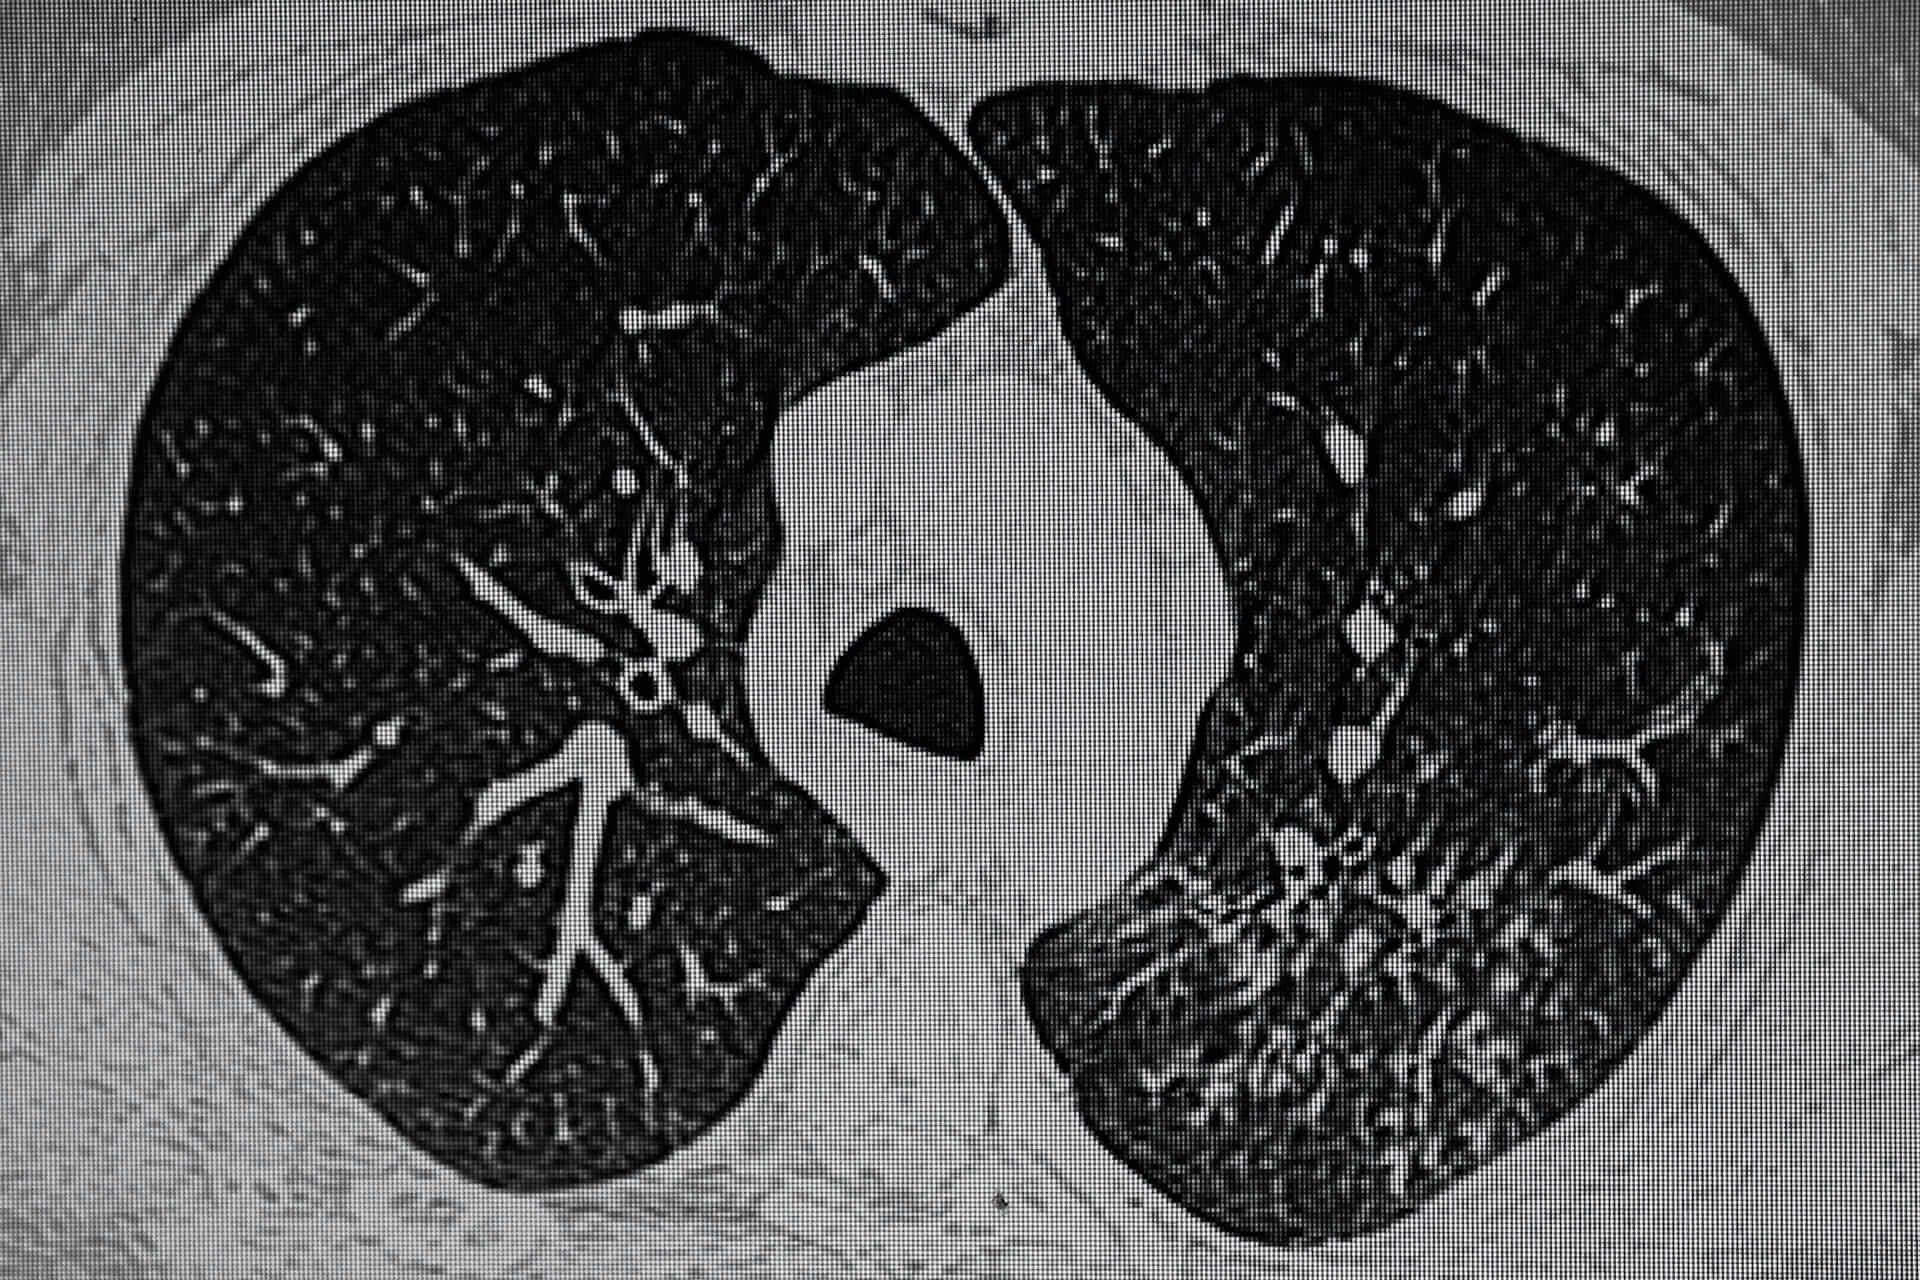

Wann muss auch die latente Tuberkulose behandelt werden?

In fünf bis 15 Prozent der Fälle geht eine latente Tuberkulose irgendwann in ein aktives Stadium über. Dies zu verhindern ist sowohl für den Einzelnen als auch für die Gesundheit der Bevölkerung ein wichtiges medizinisches Ziel.